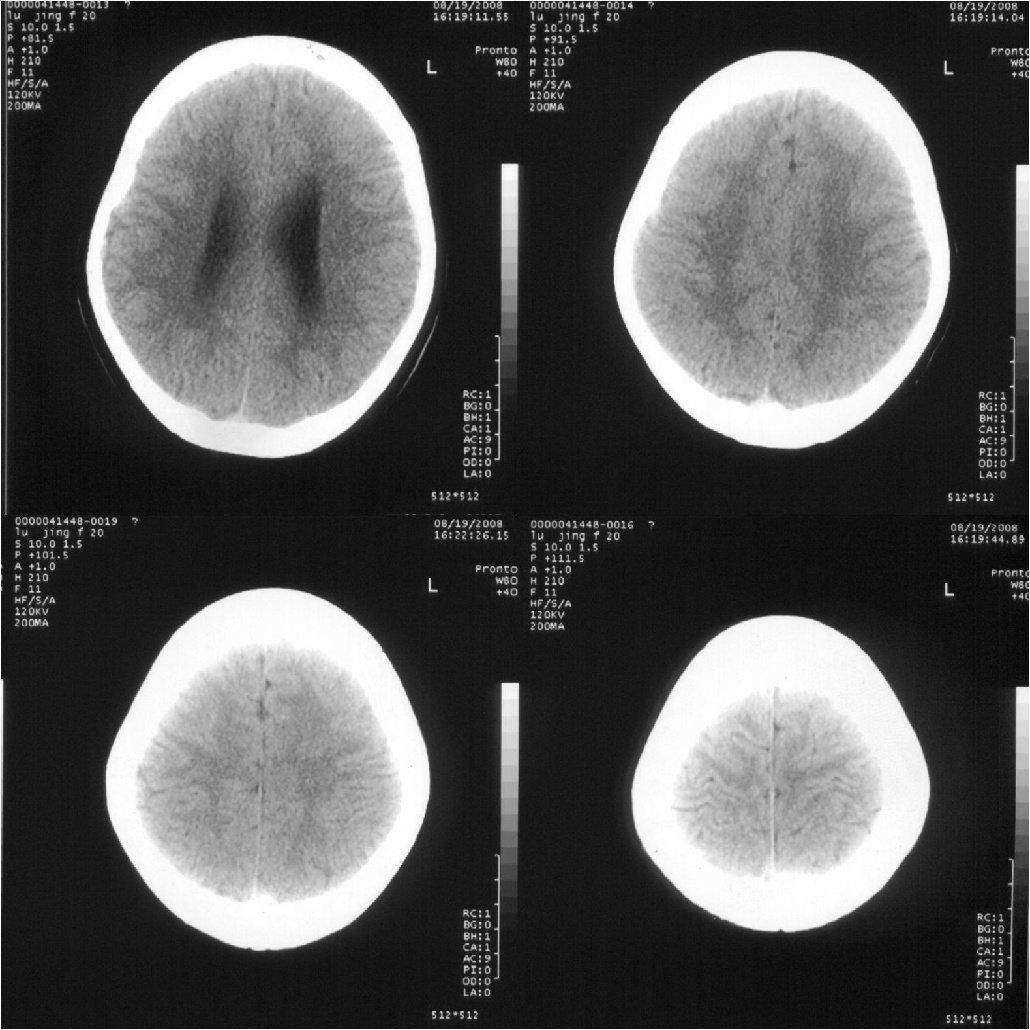

女,20岁。3天前突然恶心、呕吐,当时意识尚清楚。随后睡了一觉,醒后意识丧失,一直持续约5个小时左右才恢复意识。现在意识清楚,但一直干呕。

顶叶脑沟变浅,余未见异常!

轻度脑积水,建议mr检查.

轻度脑积水,鞍上池有低密度占位,建议做核磁

诊断脑积水有点过了,不明显

侧脑室系统轻增宽,支持轻度脑积水,建议mri

双侧脑室及三脑室轻度增大,第四脑不大。考虑幂上脑积水,可能中脑导水管不完全阻塞可能。

追踪回访:脑压测定200,现在已经正常上学

脑室稍扩大,支持轻度脑积水诊断.

十楼的朋友说鞍上池有低密度占位,我认为那是扩大的三v.